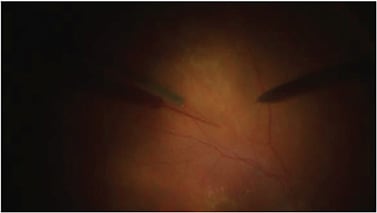

Regenxbio’s gene therapy product candidates deliver genes to cells that produce anti-VEGF molecules similar to ranibizumab to treat wet AMD using adeno-associated virus (AAV) vectors, which are non-replicating viral delivery vehicles that are not known to cause disease. The treatment involves performing a vitrectomy surgery and then administering a subretinal injection of the same AAV vector (Figure 2). Another study by the same company involves a suprachoroidal injection of an AAV vector to treat wet AMD.